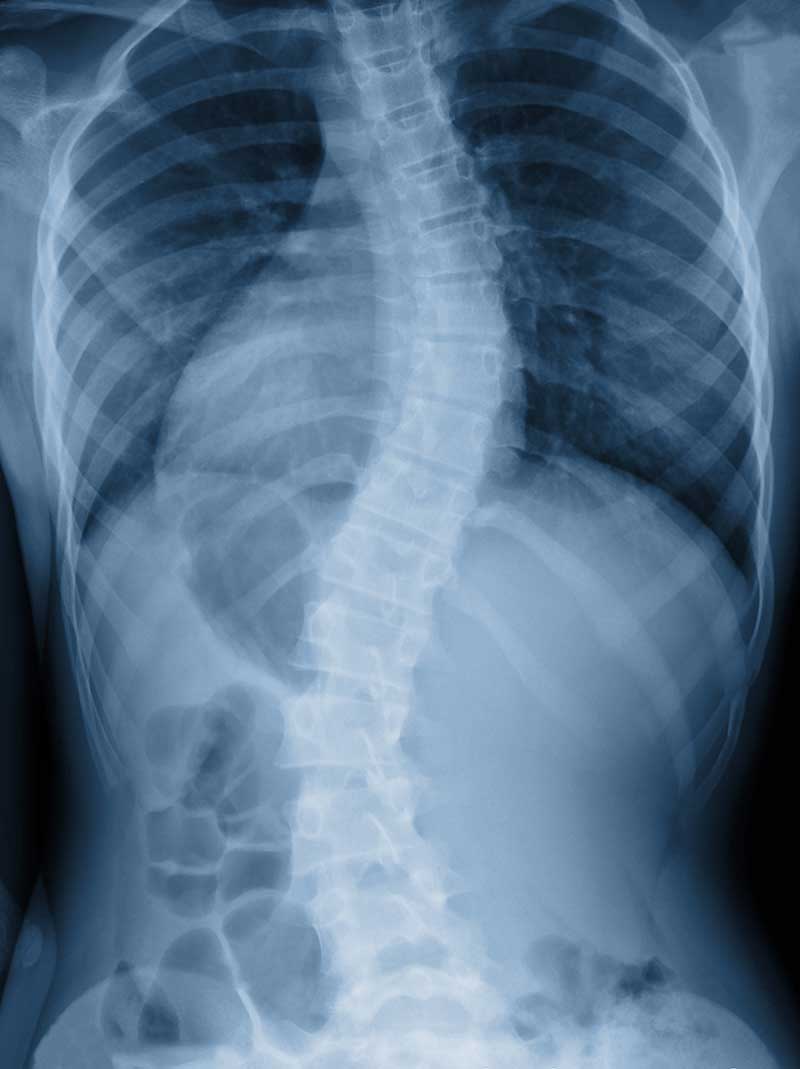

In the simplest of terms, scoliosis is a sideways curve in your spine, but there can be much more to it than that. Scoliosis typically develops in children after the age of 10 and continues to progress until the child stops growing in adulthood. Most cases of scoliosis (approximately 80% of cases) are idiopathic, which means there’s no known cause for the condition. In the remaining cases, scoliosis can be congenital or neuromuscular.

Scoliosis is diagnosed when there’s a 10-degree curvature or more in the spine. This curvature typically doesn’t cause any problems in function until it gets past the 25-degree mark, at which point pain may become an issue. Any curvature beyond 45 degrees is considered severe and usually requires surgery.